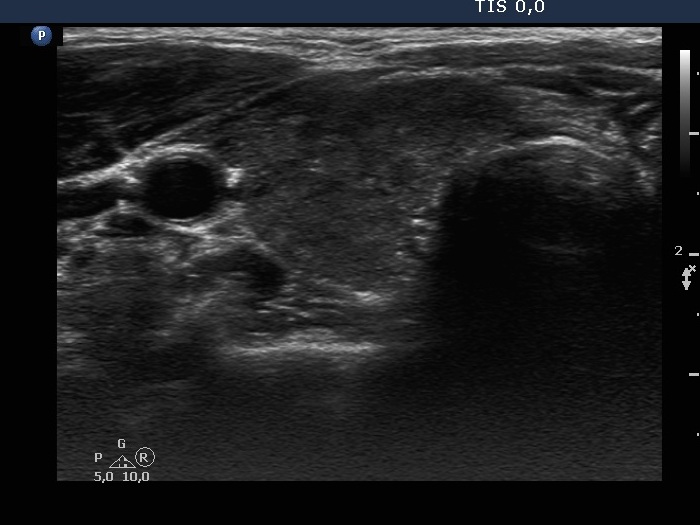

Consecutive patients with the final diagnosis of Hashimoto's thyroiditis - case 32 (717) (ultrasonographic picture 2)

Lower part of the right lobe, transverse view.